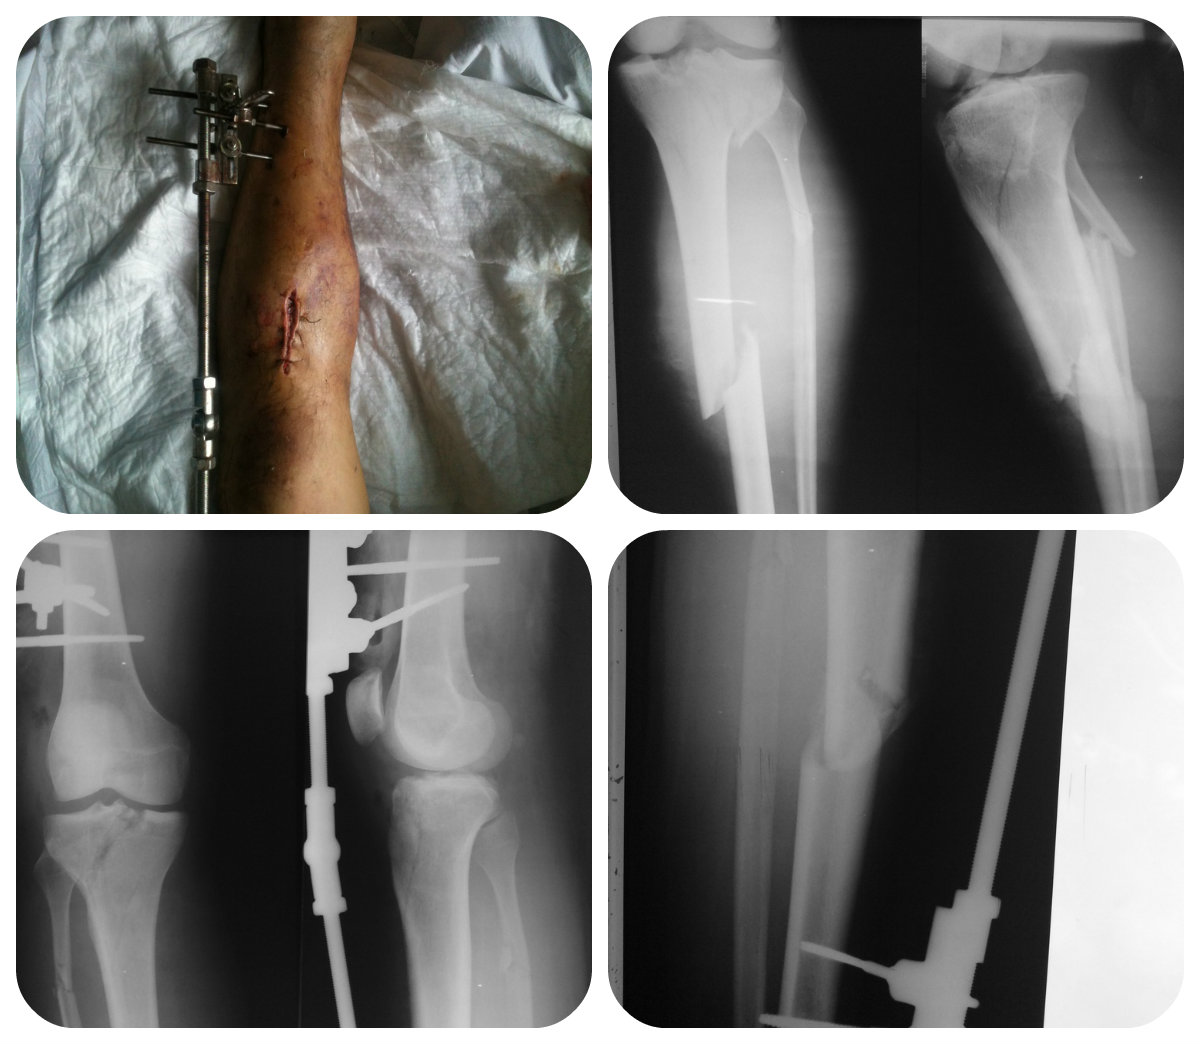

Пациент - молодой человек 32 лет. Травму получил в результате ДТП -

водитель. Получил вот такой перелом голени.

Закрытый перелом плато большеберцовой кости (на КТ - небольшой участок

импрессии в центральной зоне плато) и открытый перелом диафиза Gustillo II.

При поступлении экстренно прооперирован:

1. ПХО открытого перелома

2. ЧКДО левой нижней конечности АВФ бедро-голень

На настоящий момент - стабилен, рана голени заживает вторично.

Потихоньку готовится на окончательный синтез. Собственно, вопрос чем?)